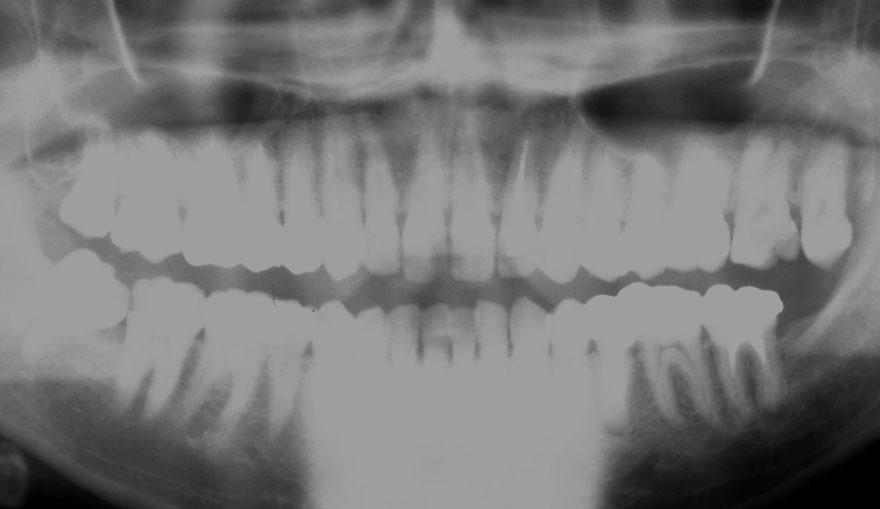

開始年齢 20代

初診時 24歳 女性

19年後 43歳

初診時 24歳 女性 平均歯槽骨喪失量:1.57mm

22年後 46歳

平均歯槽骨喪失量:1.72mm

22年間喪失量:-0.15mm

年間喪失速度:-0.007mm

(ケア頻度:1.35ヵ月ごと)